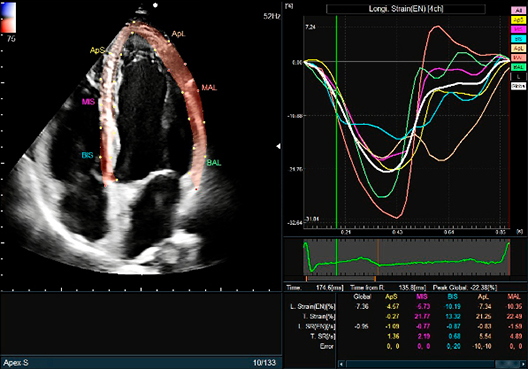

Conducts various measurements via the 2D tracking method fully automatically. One of them, Global Longitudinal Strain (GLS), is attracting attention in heart failure examinations.